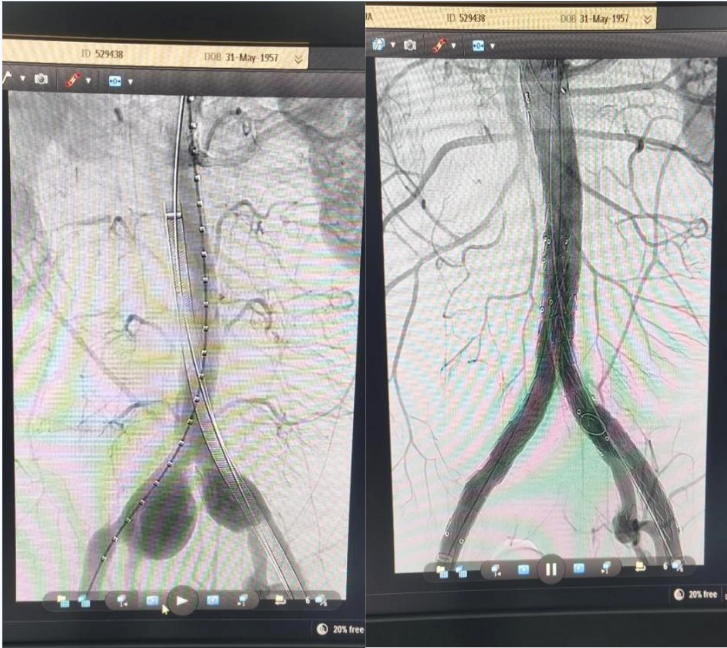

术前及术后DSA造影